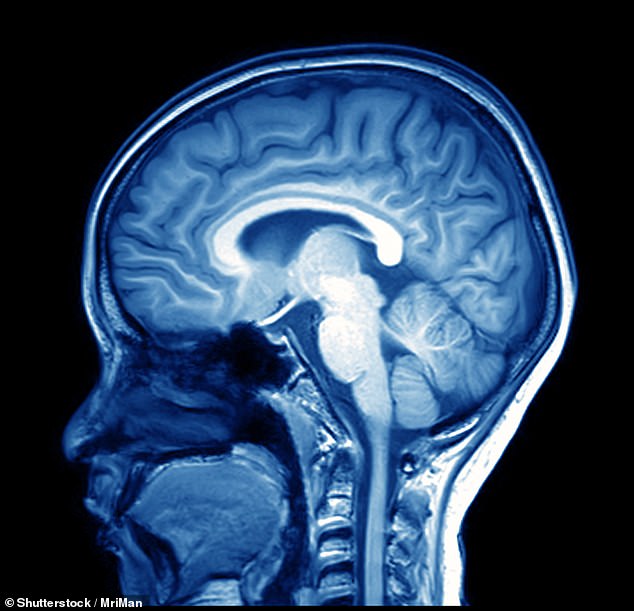

The doctors also compared MRI scans of brains from 11,399 Brits diagnosed with hypertension with scans from 11,399 Brits without high blood pressure.

These people were aged between 35-44 and 45-54 years-of-age at the time of the scan.

Medics found that people who had been diagnosed with high blood pressure had a smaller total brain volume than people without high blood pressure.

This shrinking of brain volume was worst in people who had been diagnosed with high blood pressure before they were 35.

The authors of the study believe that high blood pressure may be causing the brain to shrink in volume and this change in structure is connected to dementia.

However they added more research needed to be done to measure this trend in individuals over time, rather than a single scan.